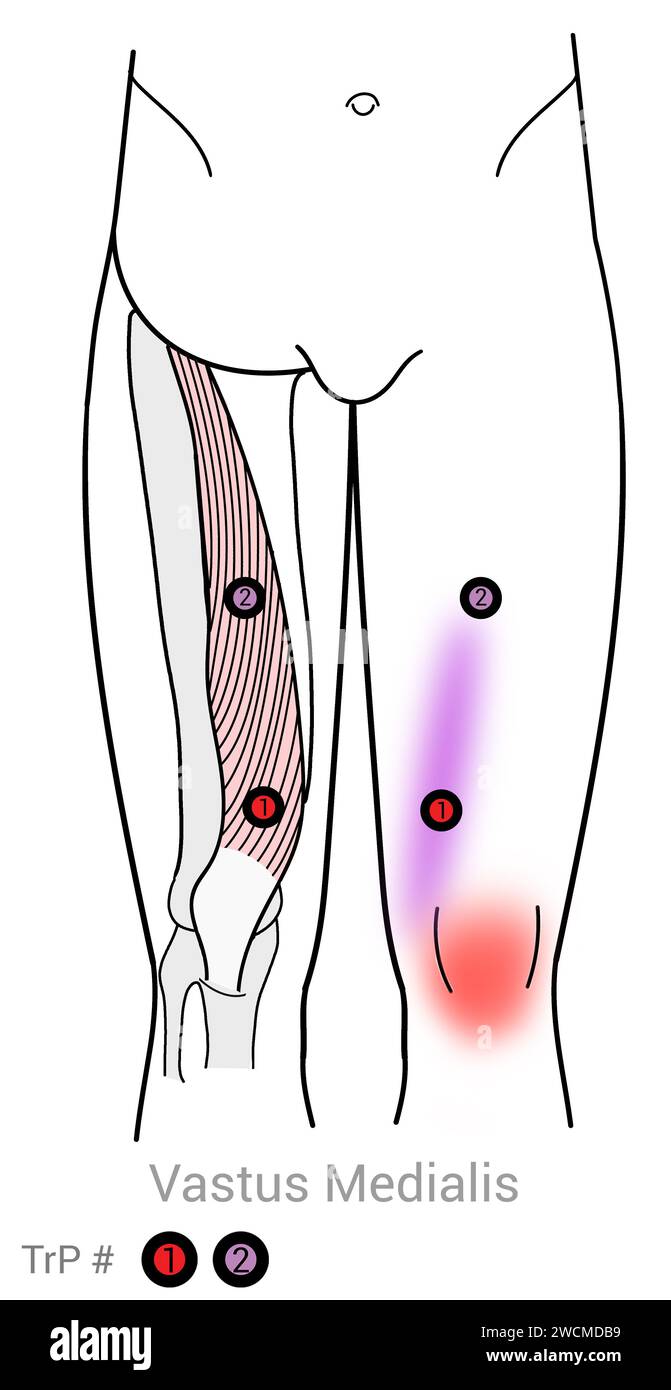

Vastus Medialis : points déclencheurs myofasciaux et localisations douloureuses associées Banque D'Imageshttps://www.alamyimages.fr/image-license-details/?v=1https://www.alamyimages.fr/vastus-medialis-points-declencheurs-myofasciaux-et-localisations-douloureuses-associees-image592977933.html

Vastus Medialis : points déclencheurs myofasciaux et localisations douloureuses associées Banque D'Imageshttps://www.alamyimages.fr/image-license-details/?v=1https://www.alamyimages.fr/vastus-medialis-points-declencheurs-myofasciaux-et-localisations-douloureuses-associees-image592977933.htmlRF2WCMDB9–Vastus Medialis : points déclencheurs myofasciaux et localisations douloureuses associées